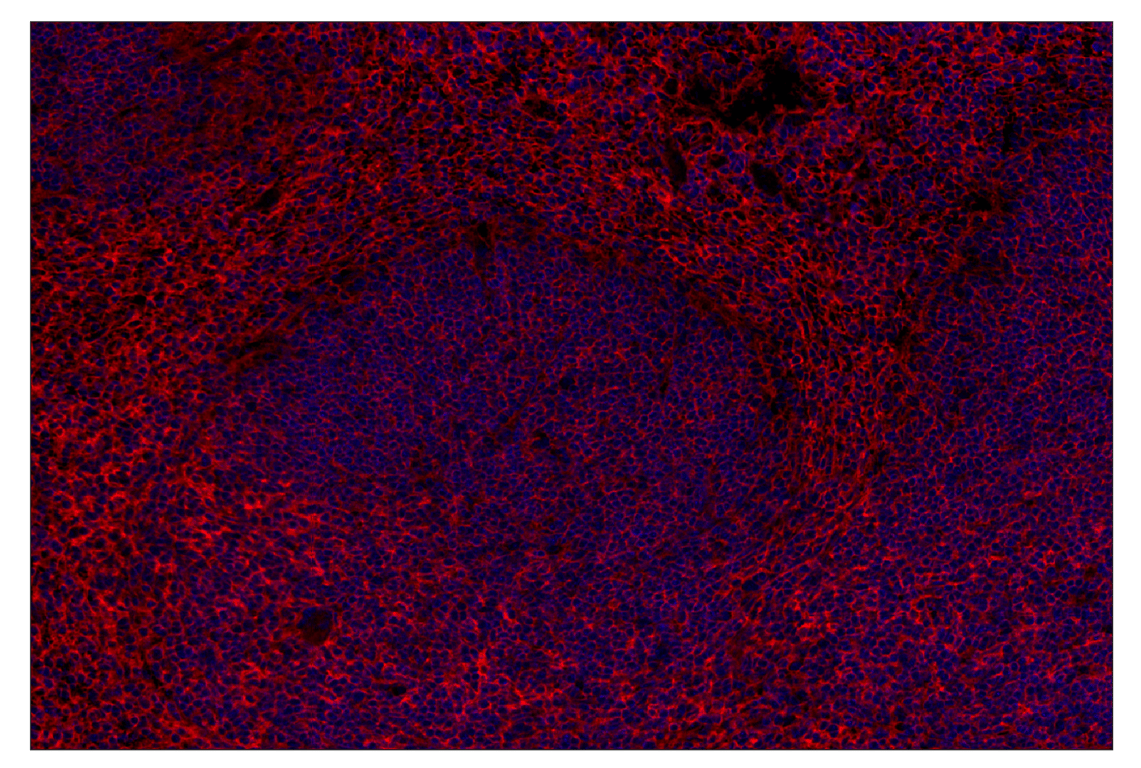

Immunohistochemical analysis of paraffin-embedded mouse spleen using CD47 (E2V9V) Rabbit mAb (Alexa Fluor® 647 Conjugate) (red) and DAPI #4083 (blue).

Immunohistochemistry Image 2: CD47 (E2V9V) Rabbit Monoclonal Antibody (Alexa Fluor<sup>®</sup> 647 Conjugate)